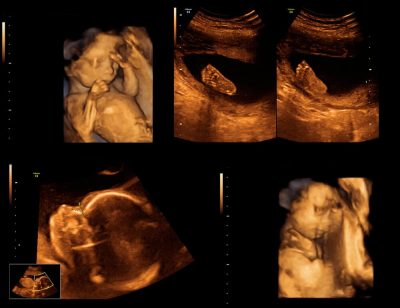

Ayrıntılı ultrasonografide anne karnındaki bebeğin her organı ayrıntılı olarak incelenir. ...

Bazı ülkelerde 2. düzey ultrasonografi veya anomali taraması olarak da adlandırılan fetus organlarını ...